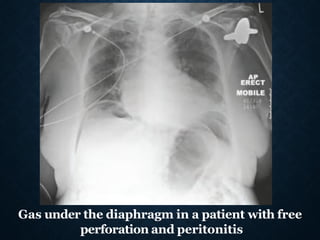

◼Erect chest radiograph

Gas under the diaphragm in a patient with free

perforation and peritonitis

Gas under thediaphragm in a patient with free perforation and peritonitis